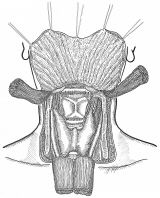

器械吻合器を用いた、咽頭部食道癌摘出後再建法

首の解剖の本と首っ引きで描きました。